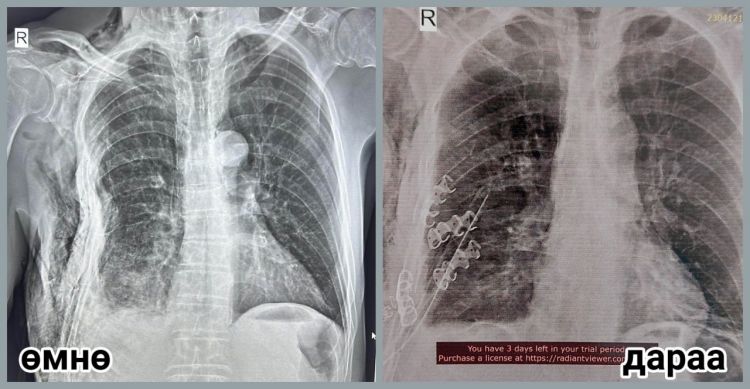

Тодруулбал, ГССҮТ-ийн мэс заслын баг бүрэлдэхүүн аймгийн нэгдсэн эмнэлгийн гэмтлийн их эмч Д.Алтангэрэл, мэс заслын их эмч Н.Энхжаргал, мэдээгүйжүүлгийн их эмч Т.Батдорж, мэс заслын сувилагч С.Ганчимэг, мэдээгүйжүүлгийн сувилагч Х.Хандсүрэн нартай хамтран мориноос унаж гэмтсэн өвчтөний хавирганы тогтворгүй хугарлыг бэхлэх мэс заслыг амжилттай хийсэн байна.

Өвчтөний биеийн байдал сайжирч, тогтвортой байгаа бөгөөд өдгөө аймгийн нэгдсэн эмнэлэгт мэс заслын дараах эмчилгээ хийлгэж байгаа аж.